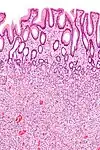

Micrograph of a Peutz–Jeghers colonic polyp – a type of hamartomatous polyp. H&E stain.